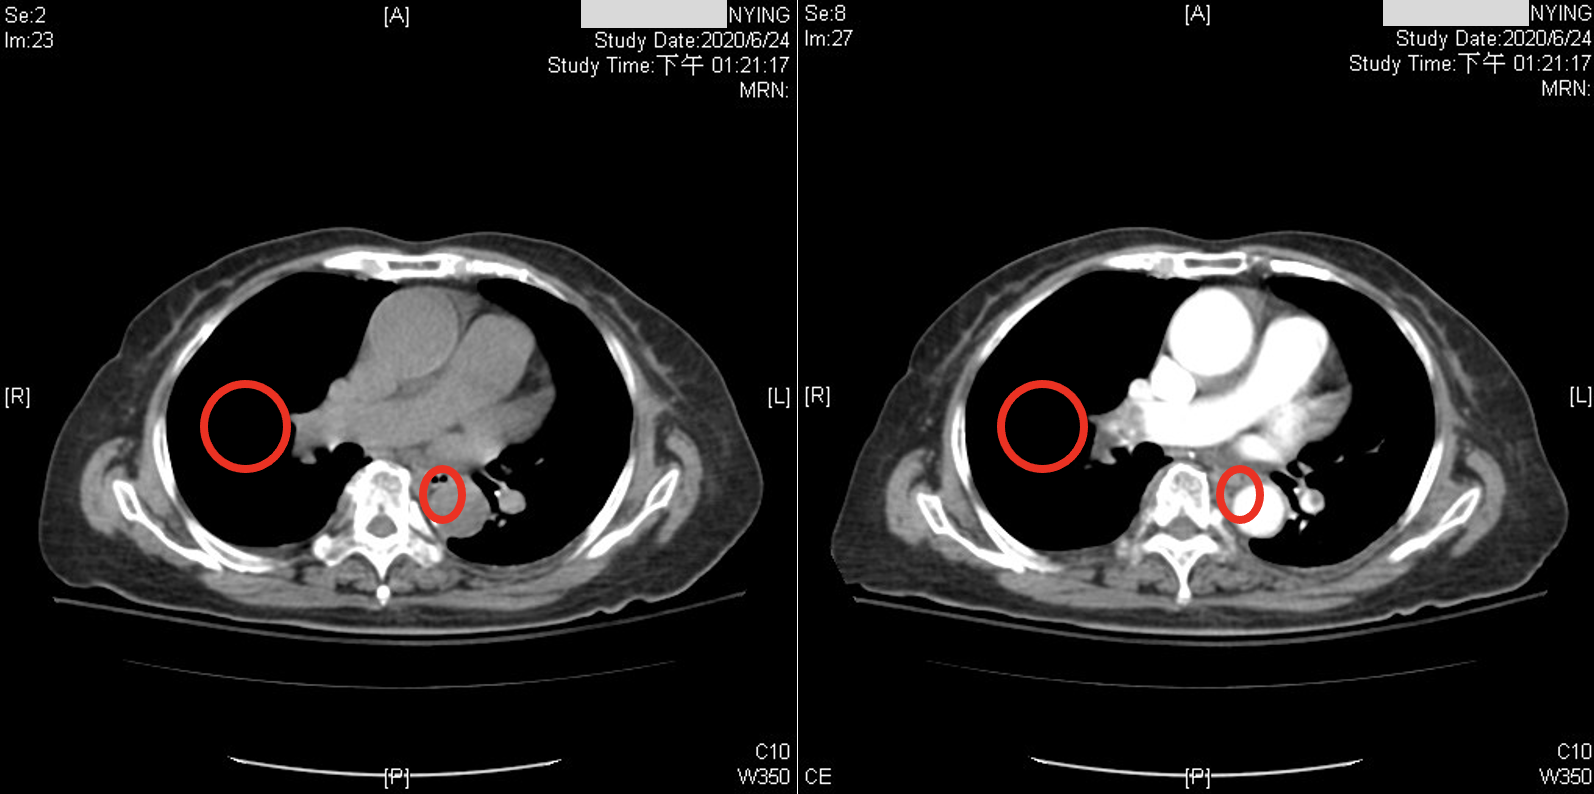

While recent studies have used CNNs to diagnose PE in CTPA. Although the accuracy could be improved from a physician’s point of view, these images have been acquired after the administration of contrast medium. CTPA images with contrast medium tend to provide clearer distinctions for diagnosis, as shown in Figure 1. However, contrast medium can have adverse effects on the body. They exert cytotoxic effects on the renal tubular epithelial cells (RTE) of the kidneys, leading to loss of function, severe cell damage, and even cell death (). Furthermore, factors such as patient history and prior surgeries can influence the impact of contrast medium on the kidneys (). Studies have confirmed that contrast medium are the most significant independent risk factor for acute kidney injury in patients with severe chronic kidney disease (). Additionally, the quality of images can be influenced by factors such as the time the contrast medium circulates in the patient’s body, the patient’s physiological factors, and the concentration of the contrast medium (). In summary, the risk associated with CTPA images is higher than non-contrast CT scans. This is because CTPA scans involving contrast medium introduce the risk of renal exposure to the contrast medium, increasing the overall risk for patients requiring related medical procedures. Consequently, this study aims to apply deep learning to classify PE in non-contrast CT scans of the lungs.